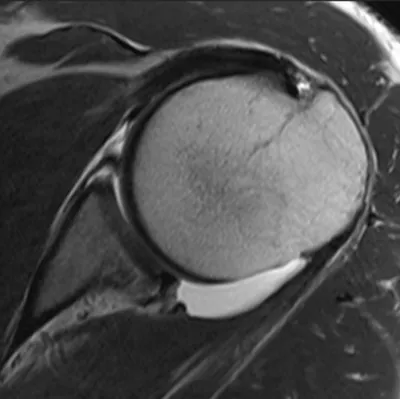

SLAP tear (Superior Labrum Anterior and Posterior)

Arthrogram

4/11/2026